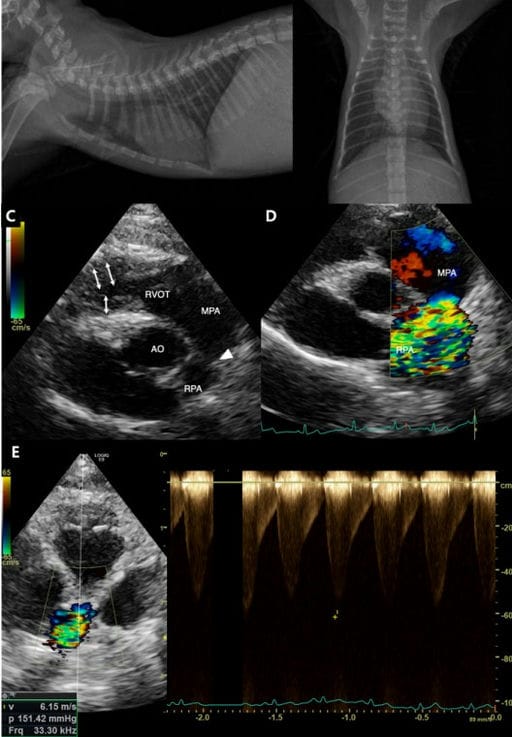

Thoracic radiography images at initial presentation (A, B) and transthoracic echocardiography images one month after

initial presentation (C, D, E). Lateral (A) and ventrodorsal (B) thoracic radiographs reveal mild cardiomegaly with mild

right atrial enlargement and a slight leftward shift of the cardiac axis. Right parasternal short-axis echocardiogram (C, D)

shows a focal narrowing between the main pulmonary artery (MPA) and right pulmonary artery (RPA) (arrowhead), with

evidence of right ventricular hypertrophy (white arrows), dilation of the MPA, a stenotic RPA, and post-stenotic dilation.

Color Doppler imaging demonstrates turbulent flow within the RPA, while the left pulmonary artery (LPA) is not visualized.

(E) The maximum velocity through the stenotic region was 6.15 m/sec, corresponding to a pressure gradient (PG) of 151.42

mmHg. RVOT: right ventricular outflow tract, MPA: main pulmonary artery, Ao: aorta, RPA: right pulmonic artery.